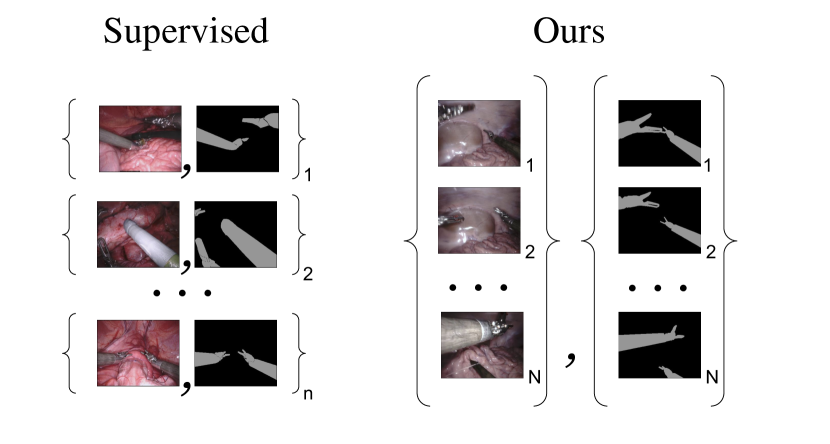

In this paper, we introduce an approach for binary surgical tool segmentation which does not need any manual annotation and only uses labels generated with imprecise kinematic model. The problem is posed as image-to-image translation [28] where we need to convert an image of surgical scene from RGB representation to semantic labels representation. Due to errors in the generated annotations that are caused by the imprecise kinematics, we are not able to train a segmentation in a supervised setting using acquired image/annotation pairs. Although we lack direct supervision in the form of image and annotation pairs, we employ set-level supervision: we are given a set of surgical images and a set of generated annotations which were created automatically without any manual annotation (see Fig. 4). By using this approach, we learn the mapping from surgical images to binary tool segmentation which is competitive with supervised algorithms that use expensive manually annotated data. This will allow segmentation models to be trained on larger amount of data and generalize better.

Figure 4: Supervised learning approach typically uses paired training data (left) consisting of training examples where every image has a corresponding manually annotated image. These datasets are expensive to collect and are usually of a small size. We instead consider unpaired training data (right), consisting of images and synthetically generated annotations using forward kinematics. This data can be automatically generated during medical procedures and can potentially be of unlimited size Nnmuch-greater-than𝑁𝑛N\gg n.